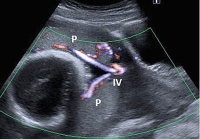

Abbildung 1a-b: Beispiele von Insertio velamentosa (a) nahe am Plazentarand, (b) distal der Plazenta. P: Plazenta; IV: Insertio velamentosa.